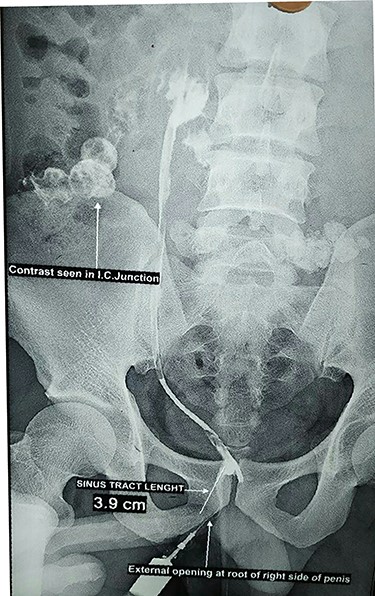

A 33-year-old male presented to the outpatient department with complaints of repeated discharge from root of penis on right side for 2 years. The condition was initially diagnosed as subcutaneous abscess with and treated with incision and drainage. The patient underwent incision and drainage two times. The discharge persisted even after repeat incision and drainage. Sinogram using water soluble contrast was planned to identify the cavity and its extension. Sinogram showed opacification of abdominal end of ventriculostomy tube superiorly with contrast spilling out from the distal ileum and opacification of the cecum, ascending colon and distal ileum. The findings were consistent with asymptomatic distal ileal perforation by ventriculostomy tube with sinus wound at the root of the penis on right side (Fig. 1).